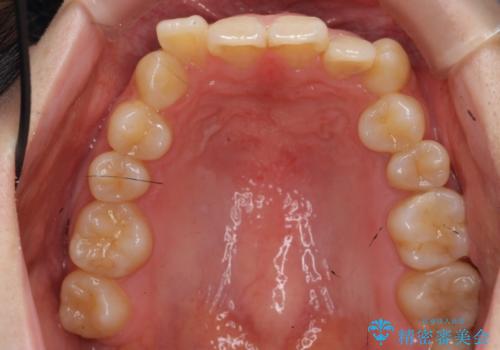

- 前歯のがたつきを主訴に来院。

下の前歯は生まれつき1本少ない状態でした。

左上の犬歯が入りきらずねじれており、かみ合わせもずれていました。

左上の小臼歯を1本抜いて治療しています。

前歯は内側に傾いており(ラビッティング)、過蓋咬合(深いかみ合わせ)を呈していました。

難しい治療でしたが綺麗に咬み合わせることができ、また前歯もしっかり当たるように治療できました。